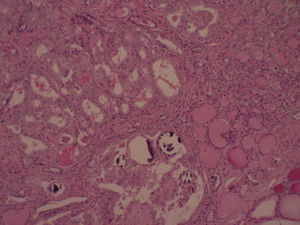

A los 7 años y 10 meses ingresó en el pabellón para la resolución quirúrgica. Se realizó lobectomía derecha, que fue enviada a biopsia intraoperatoria, informando de carcinoma papilar de tiroides, variedad clásica. Se completó la tiroidectomía total y la biopsia de la pieza quirúrgica mostró un nódulo intratiroideo en el lóbulo derecho (fig. 1), bien definido, correspondiente a un carcinoma papilar del tiroides, variedad clásica (fig. 2), de 0,5cm, con microcalcificaciones (fig. 3) y núcleos atípicos (fig. 4), sin invasión linfovascular ni perineural, ambos lóbulos con hiperplasia multinodular macro y microfolicular, con áreas de atrofia. Tamaño del tiroides normal.